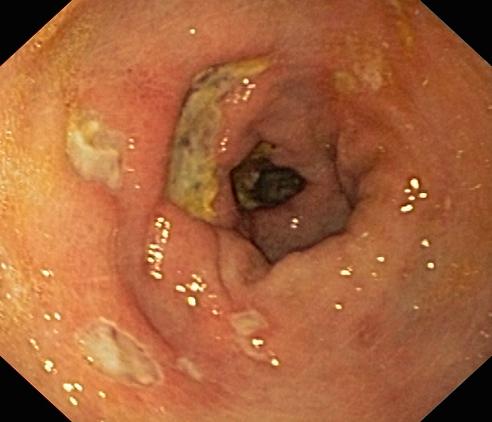

Wrzód trawienny